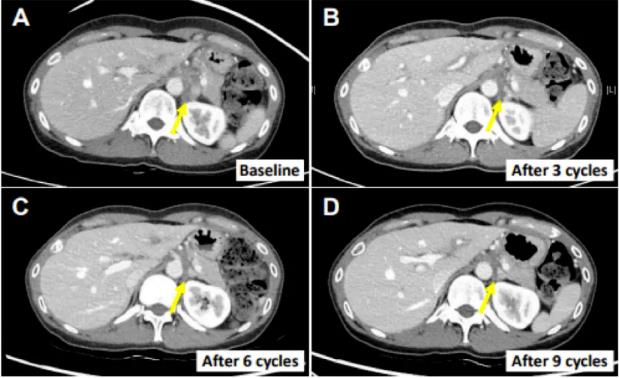

患者E0107

该例患者为40岁的女性,因胆囊炎接受胆囊切除术后被诊断为胆囊癌伴腹膜癌转移,之前曾接受过包括吉西他滨、顺铂、5-氟尿嘧啶、伊立替康和亚叶酸钙在内的化疗。在接受上述SMT-NK和帕博利珠单抗治疗后,她的转移淋巴结缩小了82.3%,并且在首次治疗18个月后仍无进展。